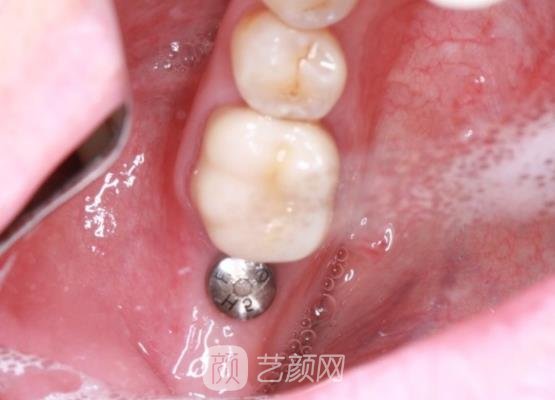

种植牙案例:

我是一个很年轻的女性,对于自身的外貌要求比较高,可是前一段时间由于一次意外的情况,导致我的牙齿缺失了。这种情况的出现,让我觉得很自卑,在人们的面前我也不敢大声去说话。我也找了很多的改变方法,终觉得种植牙手术很不错,于是我决定到医院去尝试一下。

我经过朋友为我的推荐,我选择的是张掖人民医院口腔科,这个科室在当地有着比较高的名气,我在那里预约了一位经验丰富的医生。很快就到了面诊的日子,我和父母一起来到这里做了咨询。医生的工作态度比较的严谨,而且说话口气也很温和,为我推荐了种植牙手术。

并且还对我认真的讲解了关于种植牙手术的相关资料,让我充分了解了之后,他就为我做了手术,手术过程当中由于麻醉的缘故,我并没有感觉到强烈的疼痛。手术进行的也比较的顺利,比我想象当中的要好很多。术后医生还对我交代了一些相关的注意,我一定要好好的去做。

刚刚前几天我又到医院做了一次复查的工作,医生也说我的护理做得比较好,而且也说我的体质比别人好很多,听了这样的夸奖心里面真的很开心。从此以后我又能拥有健康整齐的牙齿啦,以前面对缺失的牙齿状态,真的让我感觉到很难看,也很苦恼,我都没心情去上班了。